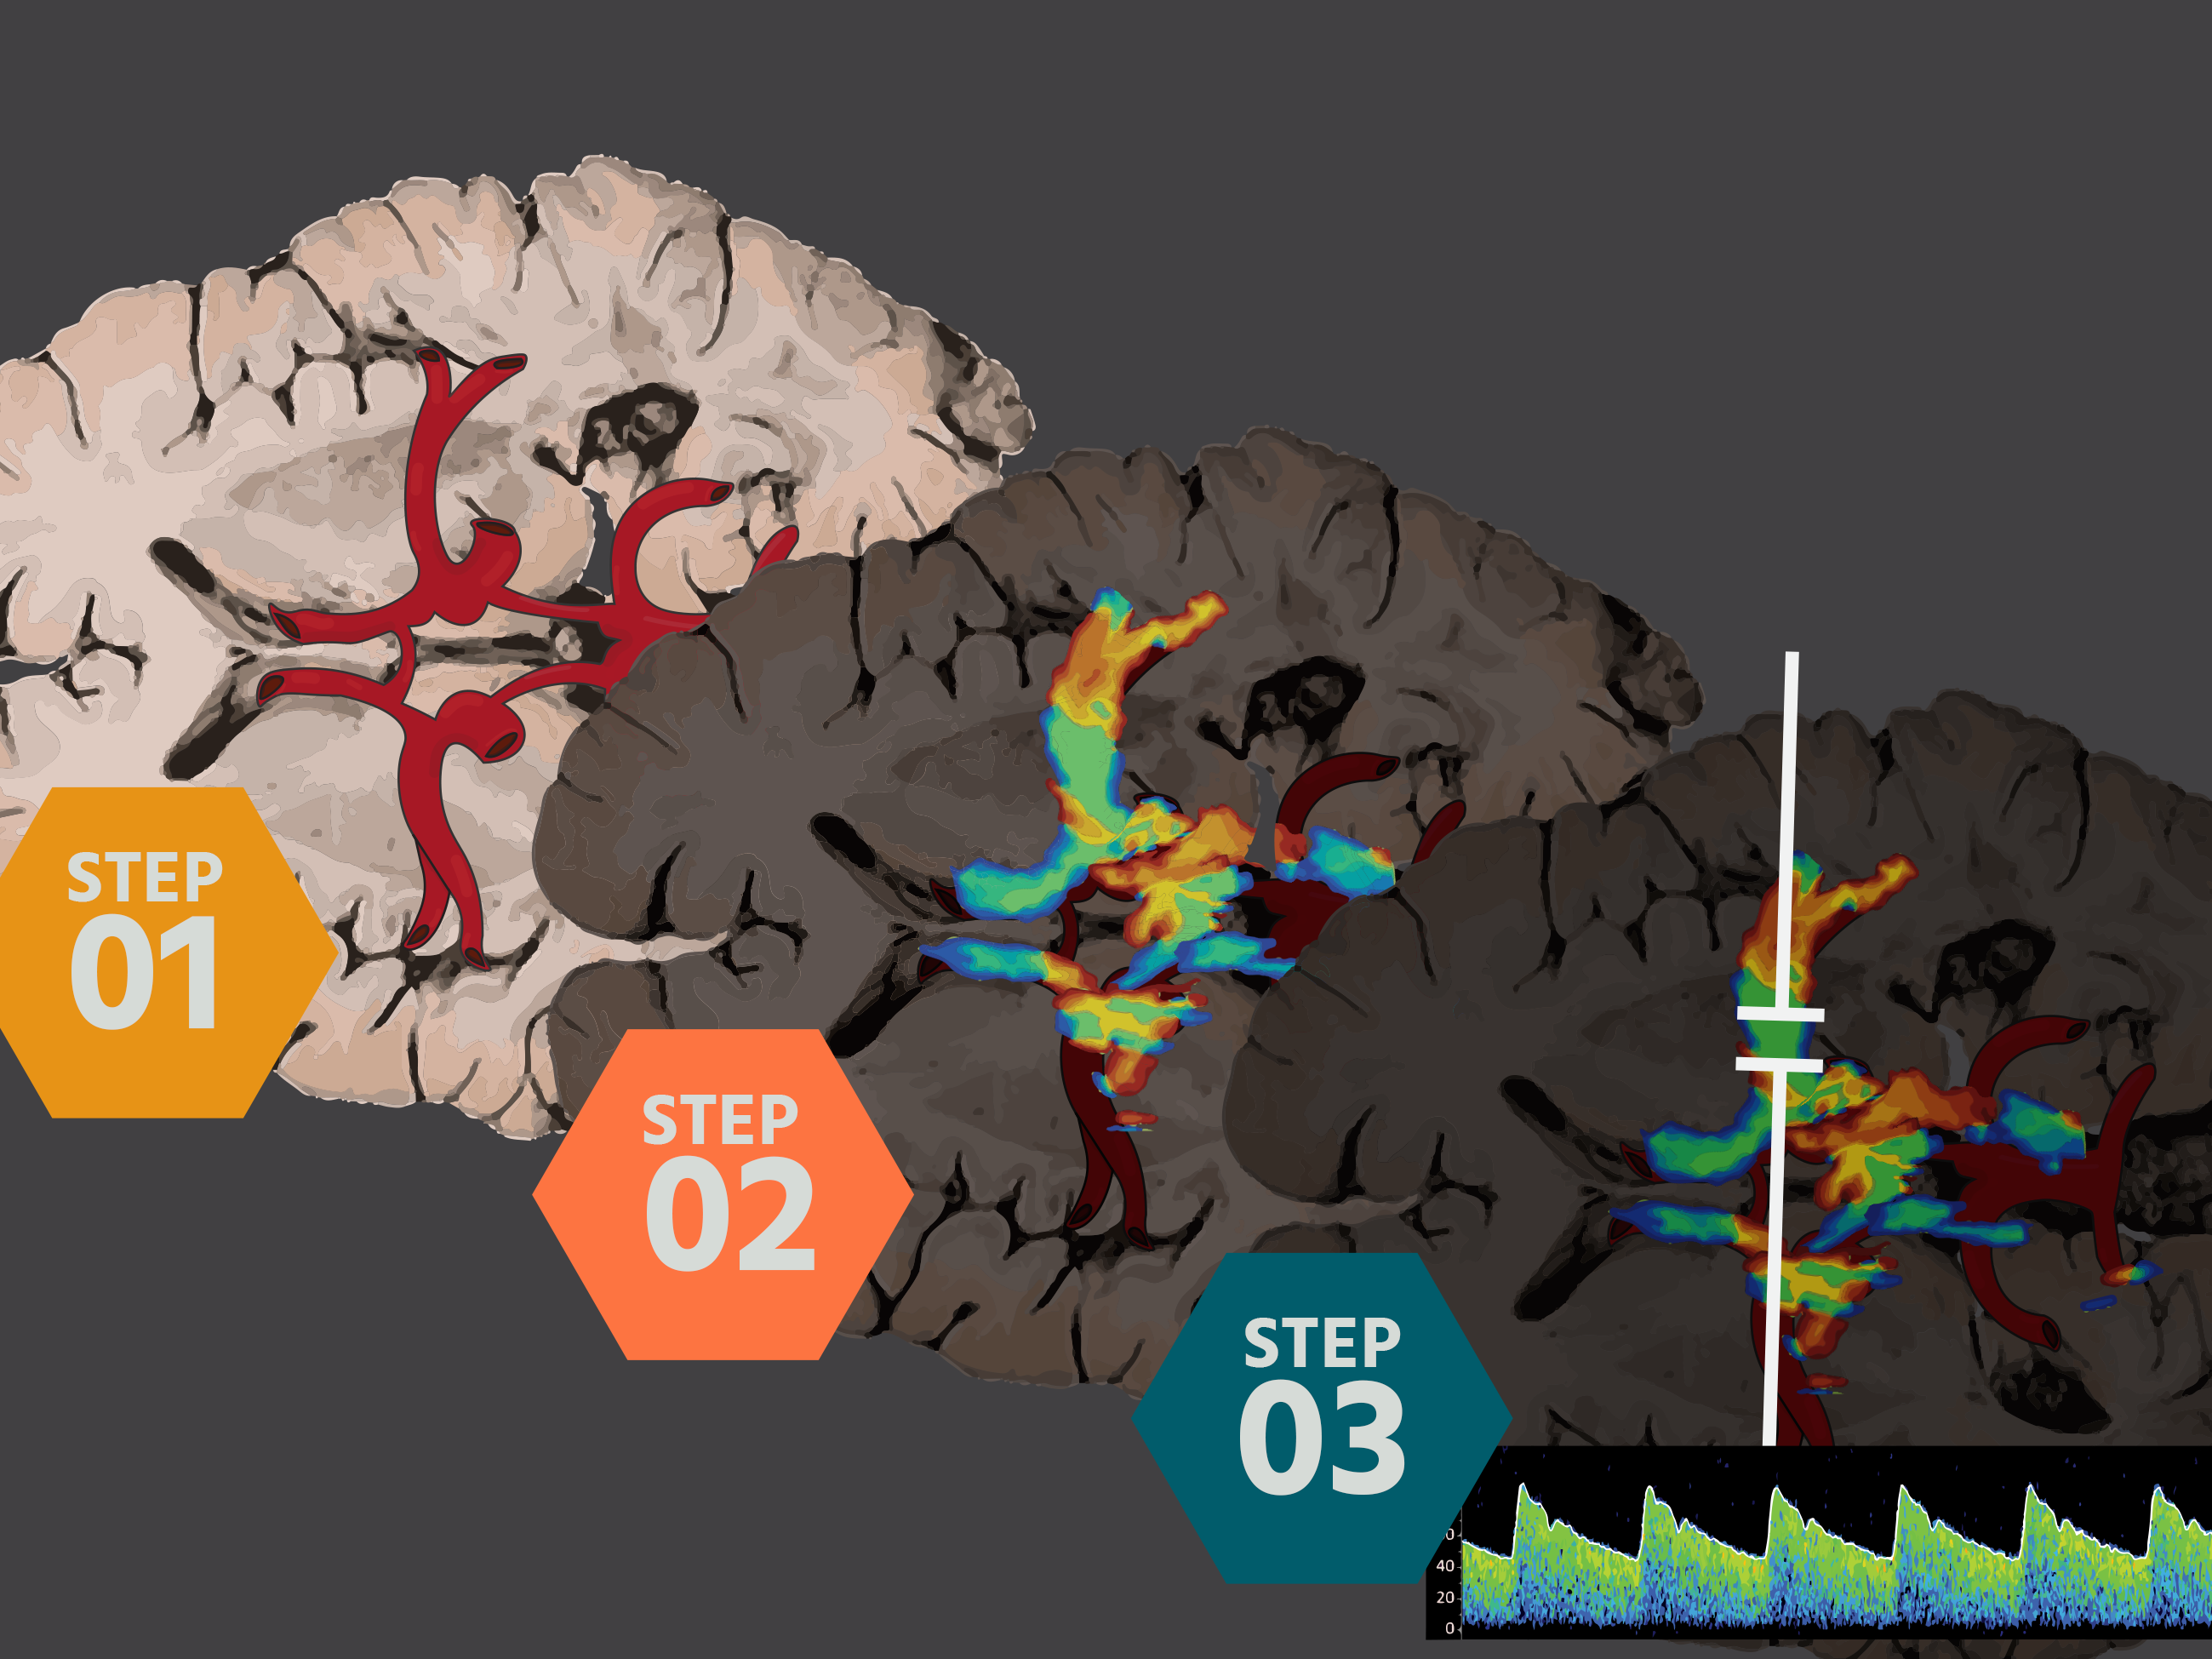

Now that you found the midbrain/mesencephalon, gently fan your probe cephalad about 10 degrees. Micromotions.

This is the Diencephalon Plane, where the dark thalami surround that sweet, sweet third ventricle like a rain cloud.

This is also where the Circle of Willis lives. But practice getting here first--finding the third ventricle can be challenging.